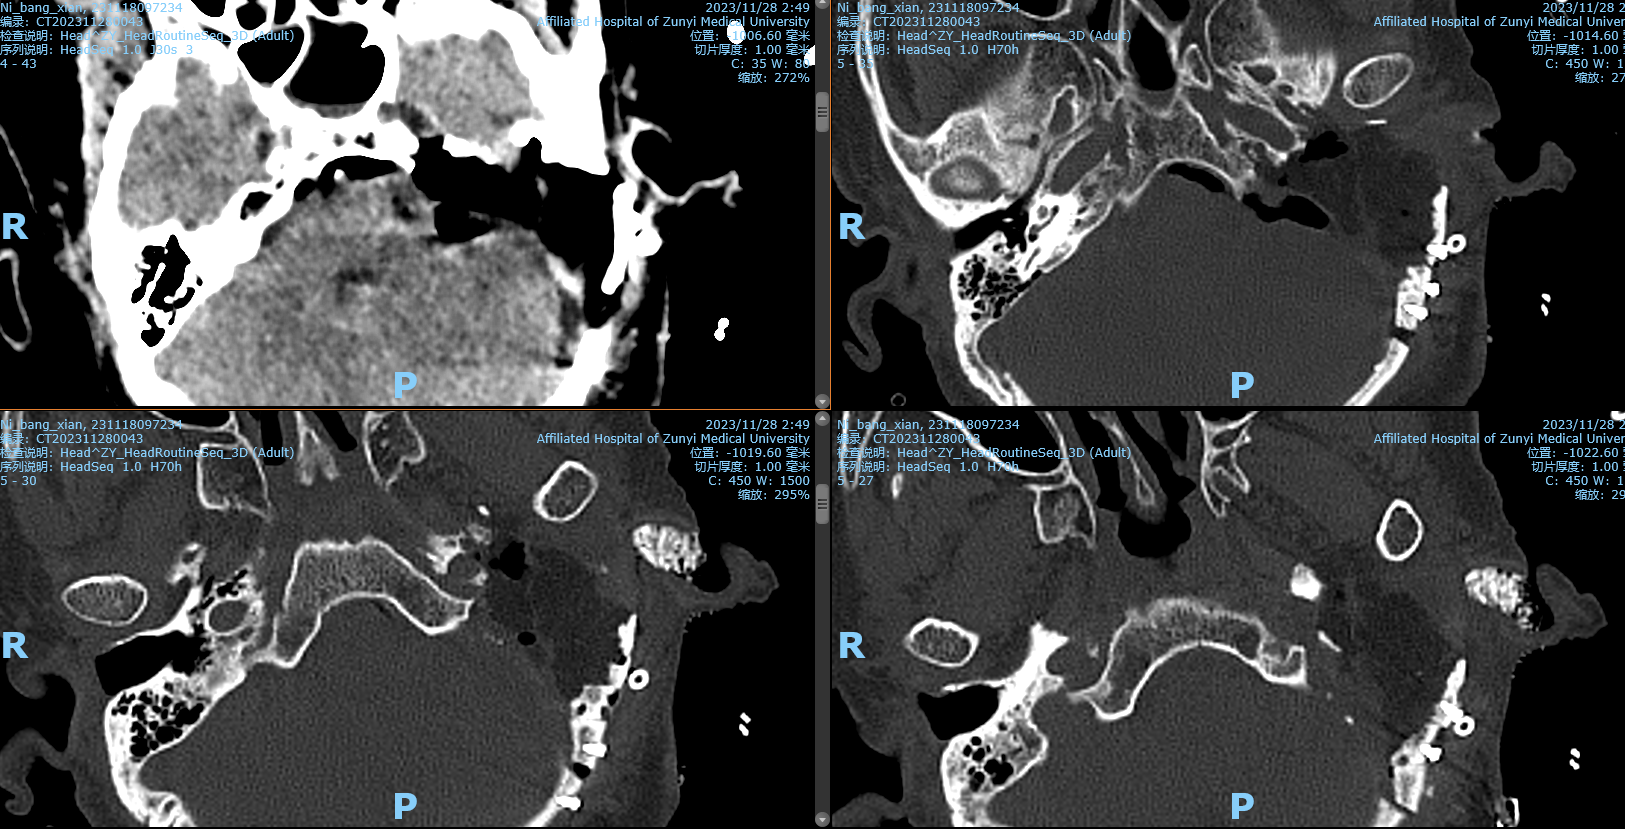

术后复查影像

阅片后考虑为左侧内淋巴囊肿瘤,侵犯岩骨,破坏面听神经,手术方案选择:左侧乙状窦前入路,窦前入路切除CPA区肿瘤,同时做岩骨次全切,术中发现面神经破坏,截取左侧耳大神经作为桥接神经,行左面-舌下神经端侧吻合,关颅后发现左侧外耳道与颅内相通,脑脊液缓慢流出,又在神经内镜下行外耳道缝扎术,术后2周出院,无脑脊液耳漏、鼻漏。术后病理后免疫组化证实为内淋巴囊肿瘤,ki-67达20%。

术式的选择应根据术前听力及肿瘤临床分级决定。Ⅰ级,肿瘤局限于迷路后区域,通常为轻至中度听力下降,为保留这类患者的残余听力,选择迷路后径路+岩骨后部切除术。Ⅱ级,肿瘤主要朝前侵犯但仍局限于颞骨内,此时迷路或内听道受累,因此患者听力呈重度下降,为完全切除肿瘤,通常选择经迷路径路颞骨次全切除术。Ⅲ级,肿瘤侵犯颞骨外结构,Ⅲa级累及颈静脉孔相关结构,推荐采用颞下窝径路切除肿瘤;Ⅲb级累及颅内,通常采用颞下窝入路结合乙状窦后入路或颅中窝入路。若肿瘤累及颈静脉球,出血风险大,术中我们可在通过闭塞乙状窦和结扎颈内静脉后,使用乙状窦隧道填塞岩下窦技术控制岩下窦出血,同时还能避免后组脑神经损伤,进而切除颈静脉球外侧壁及肿瘤。如肿瘤向外累及外耳道,同时颅内肿瘤直径>2 cm,此时可二期切除颅内肿瘤,避免脑脊液漏的发生。对于面神经未受累及的早期肿瘤患者,术中应注意避免损伤面神经及其骨管;对于面神经受累及的患者,应切除受累面神经,并同期行面神经-耳大神经吻合术或面神经-舌下神经吻合术。采用颞下窝径路时,为了更好地暴露肿瘤,可将面神经部分前移位或使用面神经骨桥技术。累及颅内的患者,可根据肿瘤大小,同期或分期切除颅内肿瘤。为预防术后脑脊液漏和颅内感染,术中可用人工脑膜、肌肉及脂肪修补脑脊液漏,用肌肉及骨蜡封闭咽鼓管,将蒂在后方的肌骨膜瓣同前方腮腺后缘缝合,并封闭外耳道。